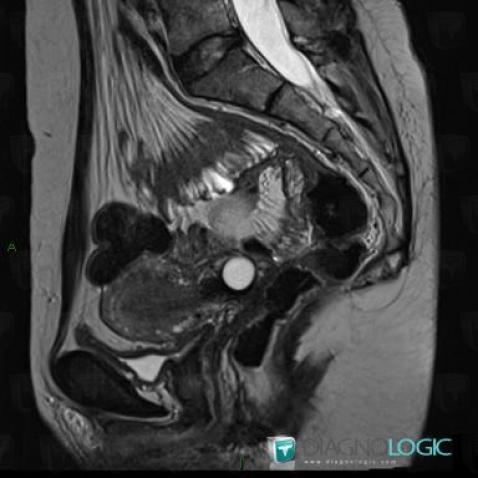

Teratoma, Adnexa / Ovary fallopian tube, MRI

Here is the specific information in the key image above:

- Diagnosis Teratoma (link to Dermoid cyst), Location(s) Adnexa / Ovary fallopian tube, with gamuts T2 WI hyperintense adnexal mass

Nabothian cyst, Uterus, MRI

- Diagnosis Nabothian cyst, Location(s) Uterus, with gamuts Cervical mass